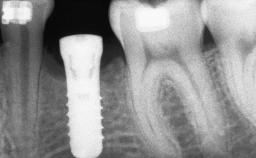

Ridge Preservation and Implant Placement for a Fixed Dental Prosthesis After a Car Accident

It is well known to clinicians that any removal of teeth will, over time, cause the dimensions of the alveolar ridge to be reduced by resorption of the bundle bone and by changes related to external modeling. This development is particularly evident in the crestal region with its thin buccal bone that consists of bundle bone almost entirely. The facial bone will rapidly resorb as blood supply from the periodontal ligament gets disrupted (Araújo and Lindhe 2005). There is no reason why traumatic tooth loss should not have the same consequences. It takes more than achieving implant osseointegration for a treatment outcome to be considered successful. No deficiency of bone or soft tissue is acceptable when an ideal esthetic outcome is the goal. Several articles (Sanz and coworkers 2011; Vignoletti and coworkers 2011) have reported on techniques of improving the alveolar ridge for implant treatment, notably focusing on protecting tissues from resorption.

Bone Augmentation Horizontal|Simultaneous|Sinus Floor Elevation|Staged

Bone Volume Deficient vertically or deficient vertically AND horizontally